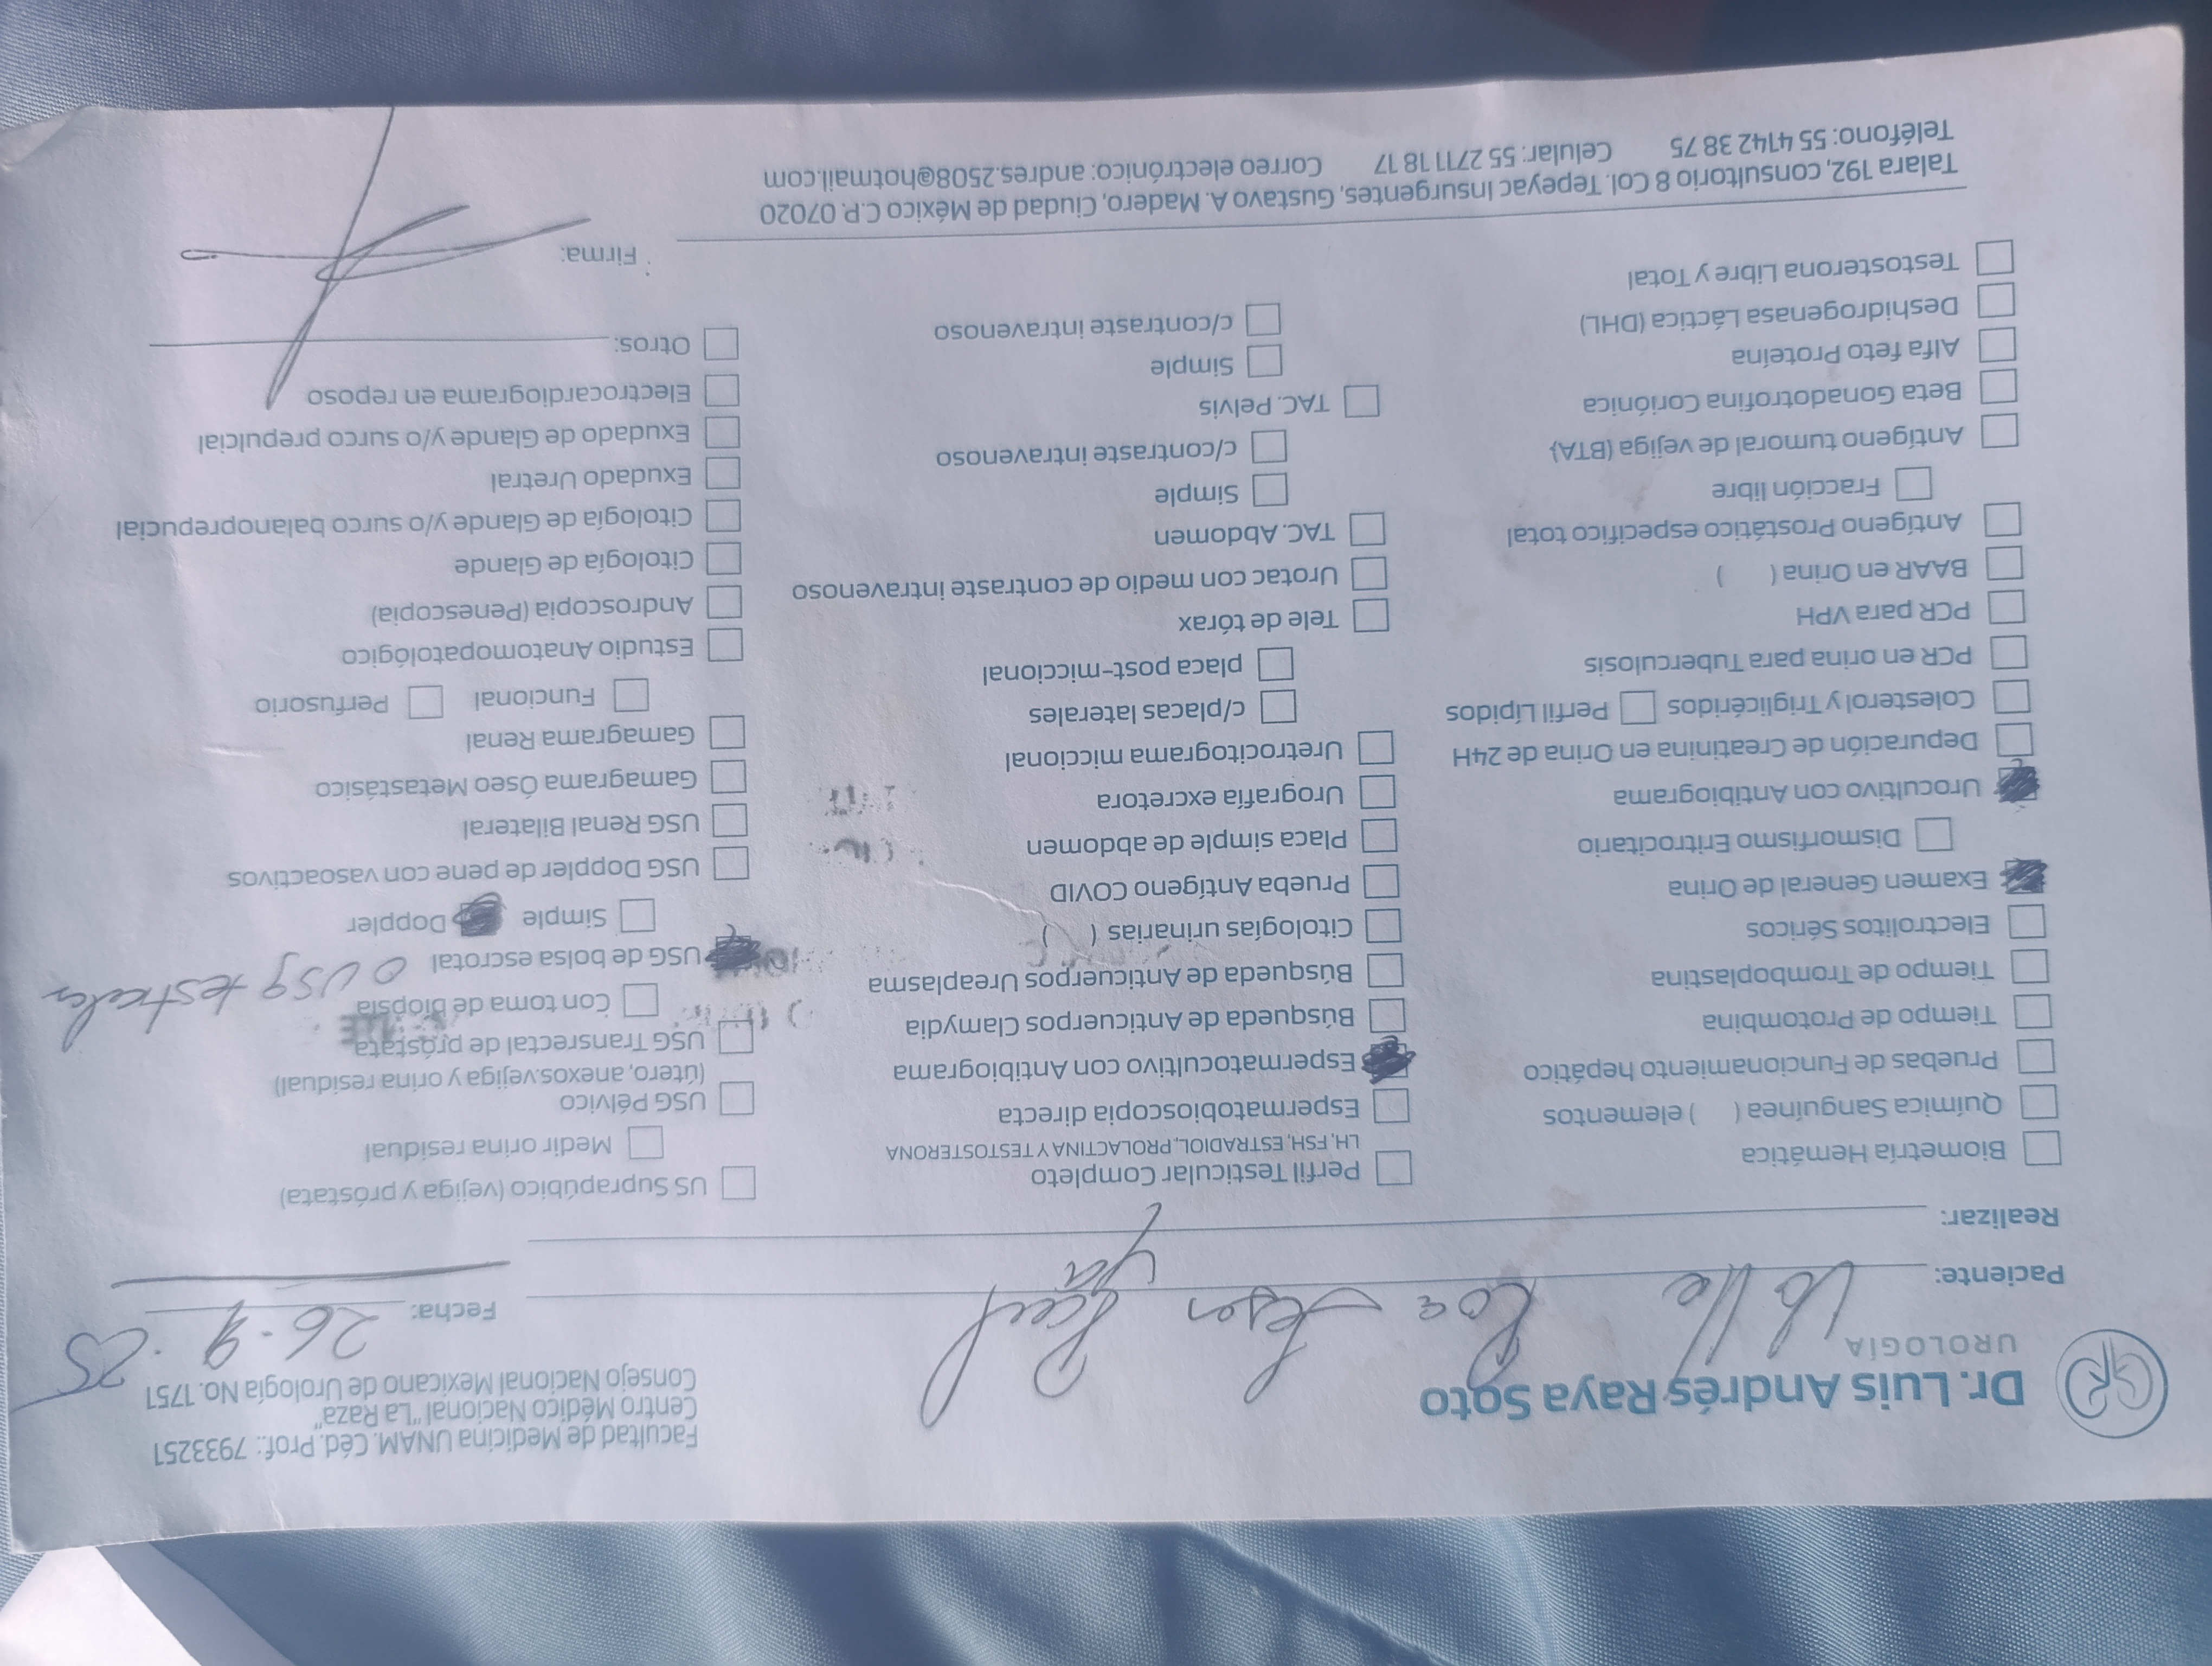

Hola me Llamo Raúl ,tengo 25 años , soy de la CDMX , me atrevo a pedir está ayuda , ya que desde hace unos meses empecé a sentir fuertes dolores en la zona de los testiculos, me hicieron estudios Doppler Testiculares, me detectaron Varicocele de Grado 4 en ambos testículos y microlitiasis testicular en ambos testículos y también tengo hernias en ambos conductos de los testiculos, sufro de fuertes dolores en ambos testículos , eso también está provocando que mi próstata este inflamada, no puedo mantenerme mucho tiempo parado o sentado, me duele mucho al orinar aveces con sangrado, llega el punto en que no puedo ya controlar la orina sale por su cuenta propia, no me atiendo en el IMSS porque el tiempo de espera es mucho , fui a médico particular y me dijeron que ya era urgente la operación porque la sangre no está llegando a los testiculos y se están muriendo, en estos momentos corro riesgo de Esterilidad , y las hernias si no se tratan pueden abrir mas y provocar que los intentos bajen por los conductos de los testiculos y sea una urgencia muy grava y riesgo de una extirpación del intestino si eso llega a pasar , pido su ayuda para poder llegar a esta cantidad, ya que en mi situación es muy difícil poder conseguir todo el dinero.